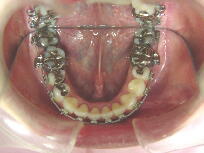

症例3 (30代 女性) 右下顎切歯先天性欠如

左右上顎第一小臼歯・右下顎第一小臼歯抜歯例

![]() ![]() ![]()

初診時